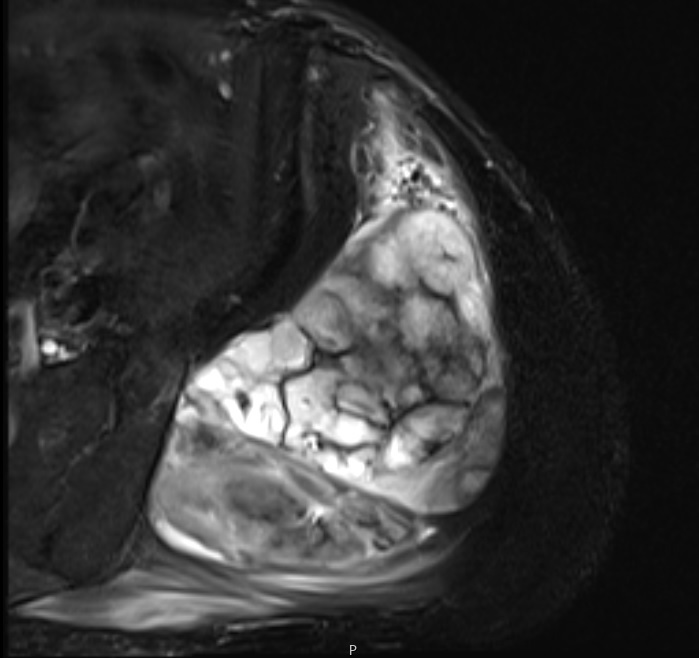

Fig. 3 Axial fat suppressed T2-weighted MR image demonstrates a large heterogeneous mass with multiple thick internal trabeculations. Fatty areas suppress on T2 weighted fat suppressed areas